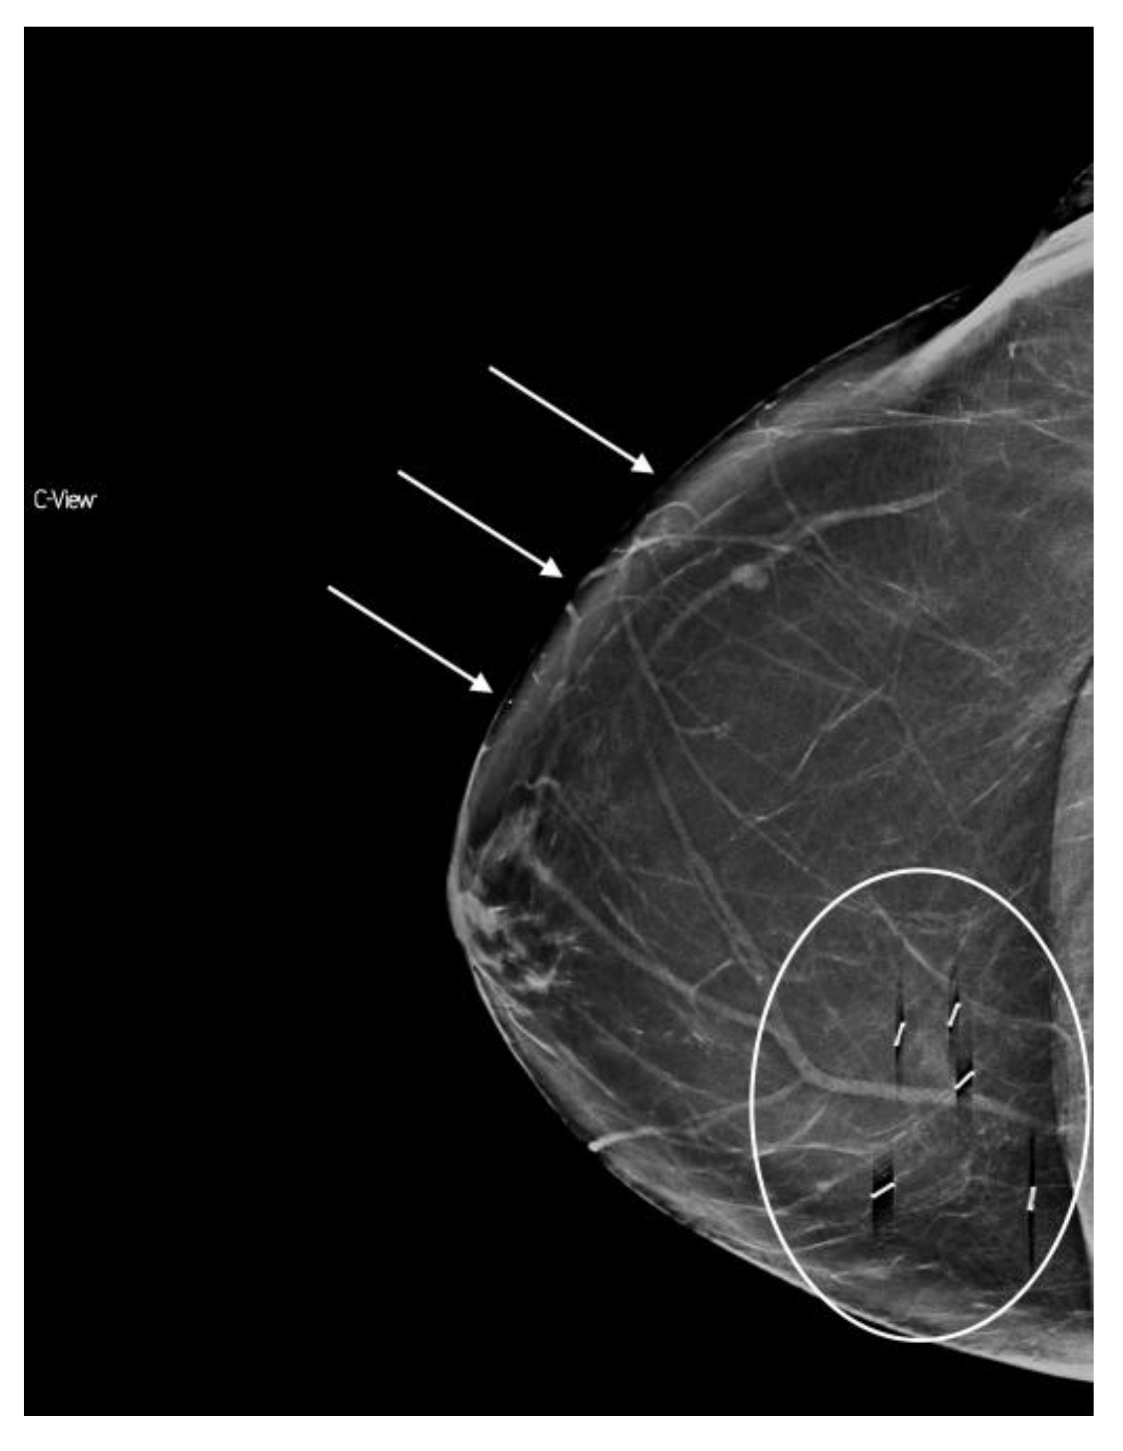

6.5. Artifacts

Awareness of a few artifacts unique to s2D can ease familiarization with synthesized images. A bright-band artifact may be observed with s2D as a layer of brighter tissue, which follows the curvature of the breast at the subcutaneous level. (Figure 6). Typically this area contains fatty tissue and lesion detection can still be made readily. Additionally, especially in very dense or very thick breasts, because higher radiation dose is needed, the detector can get saturated at the skin line and cause loss of resolution of the skin line. (Figure 7).

Figure 6.

Bright band artifact (indicated by arrows) can be seen along the curvature of the medial breast on synthesized mammography. (a) 2D FFDM (no artifact) (b) s2D with Bright band artifact.

Figure 7.

Loss of skin resolution or “skin burnout” (indicated by arrows) can be seen on synthesized mammography. (a) 2D FFDM (no artifact) (b) s2D with skin burnout artifact.